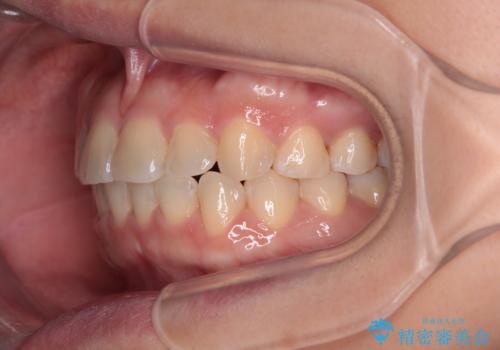

舌の突出癖により上下前歯が開咬となりましたが、舌のトレーニングと顎間ゴムの使用により、元々の被蓋関係に改善することができました。

アンカースクリューを用いて、出っ歯仕上がりを回避し、正中位置も改善することができました。